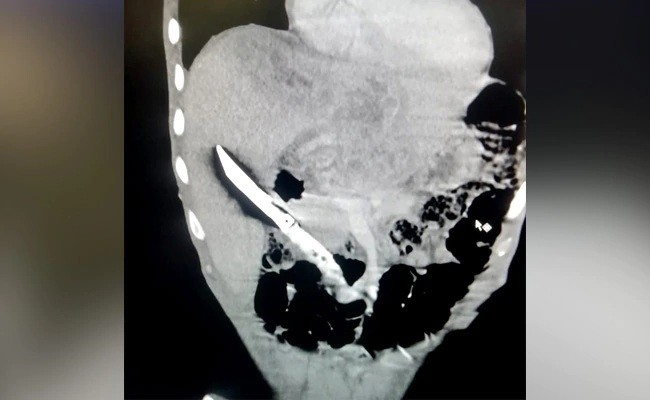

医院的腹部超声波和X光检查显示 , 一把小刀的刀刃正卡在肝脏上 。 全印度医学研究院的达什(Nihar Ranjan Dash)医生说:“由于预见到取出异物的难度 , 那里的医生就把病人转到了全印度医学研究院的胃肠外科和肝脏移植科 。 ”

医生们解释道 , 当病人在紧急情况下入院时 , 他们进行了超声波、CT扫描和其他检查 , 以了解刀的确切位置和周围重要器官的关系以及它可能引起的并发症 。

“在CT扫描中 , 我们发现刀锋完全在肝脏内 , 刀柄在十二指肠内 , 十二指肠就是小肠的第一部分 。 那把刀实际上穿过了十二指肠 , 刺进了肝脏中 。 它导致了出血、感染、肝脓肿和脓毒症 。 他的血红蛋白水平很低 , 开始出现脓毒症 , 体重减轻 , 右胸积水 。 ”达什医生说道 。